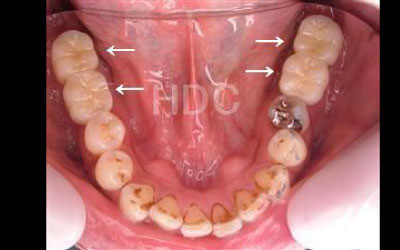

2 歯が傾いてくる、落ちてくる

歯はお互いに支え合ってバランスを取っています。ですので、歯が抜けるとその支えがなくなり、抜けた部分の隣の歯が倒れたり、上の歯が下に下がってくることがあります。

歯のズレが軽度であれば、調整や詰め物で対応できる場合がありますが、大きく傾いてしまっている場合には、矯正治療や被せ物による対応が必要になることもあります。ズレが進行する前に、早めに検査と治療を受けることをおすすめします。